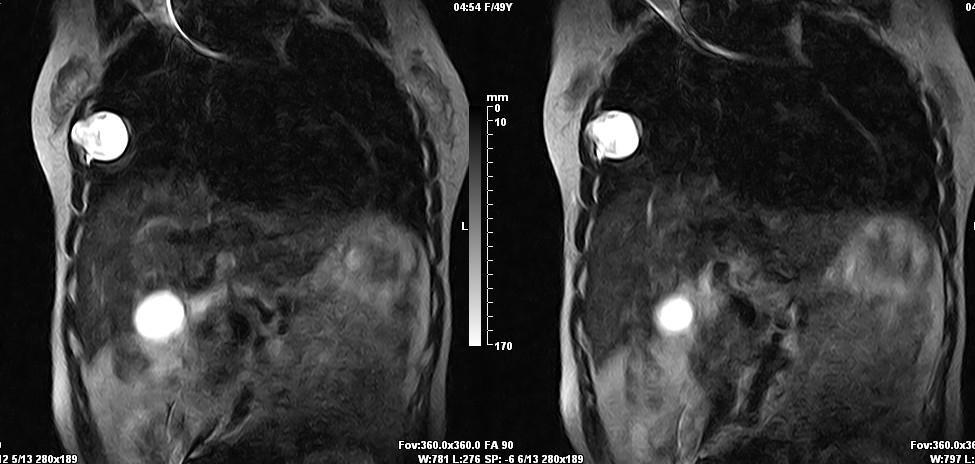

女,49岁。三年前因胸部不适在外院行CT检查诊断报告:右胸壁占位病变,考虑胸膜间皮瘤可能性大。现病人到我院检查了解情况。算是较典型的病变吧?大家看看MR比CT优点在哪里?

病检神经鞘瘤

病检是神经鞘瘤。

液性信号符合神经鞘瘤囊变。